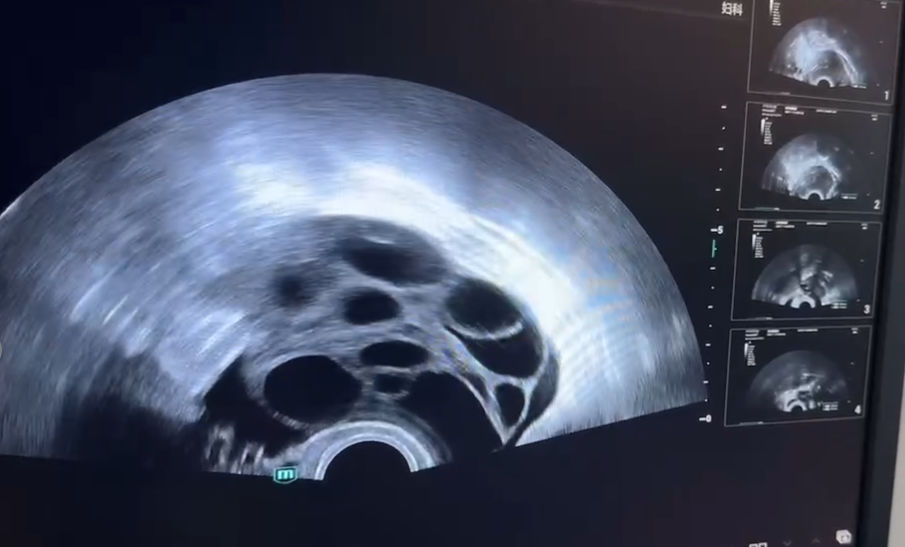

(b超影像中的卵泡)

女性每个月经周期,会有一批卵泡自然发育,最终通常只有1-2个优势卵泡发育成熟并排出,其余会自然闭锁。

冻卵促排的原理,就是把本月那些原本注定要“闭锁”、浪费掉的卵泡一起“救”回来,让它们共同发育成熟。促排卵药物并没有调用未来几个月的卵子库存,更没有加速卵泡库存在未来的耗竭速度。它只是在时间维度上对本月资源进行了一次“优化利用”,而非对总长度的“提前透支”。